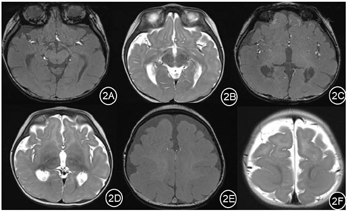

实验室检查提示血常规、血生化、血氨、血乳酸等检查均无异常。视频脑电图(图1)提示:背景弥漫性慢波增多,全脑区可见大量高度失律。头颅磁共振成像MRI(图2):①巨脑回及无脑回畸形②双侧额顶叶硬膜下间隙增宽③双侧侧脑室增宽④透明隔间隙。Gesell发育量表测评:DQ 39.1。

根据患儿临床表现及脑电图高峰失律图形,诊断为West综合征。为进一步明确病因,经福建医科大学附属协和医院医学伦理委员会批准(批准号:2020KY0108),患儿监护人签署知情同意书,采集患儿及其父母外周血行基因全外显子测序(whole exome sequencing,WES),并行Sanger测序进行验证。结果显示(图3)患儿染色体Chr1:39460714位点上MACF1基因存在新发突变(de novo),NM.012090.5:exon 87 c.15266T>C(pMet5089Thr),其父母该位点为野生型,经过Sanger测序验证证实,患儿为上述变异的错义突变,而其父母均未发现变异,符合常染色体显性遗传方式。正常人群数据库中未发现该变异。参照美国医学遗传学与基因组学学会(American College of Medical Genetics and Genomics,ACMG)评级为疑似致病性变异(likely pathogenic, LP)。